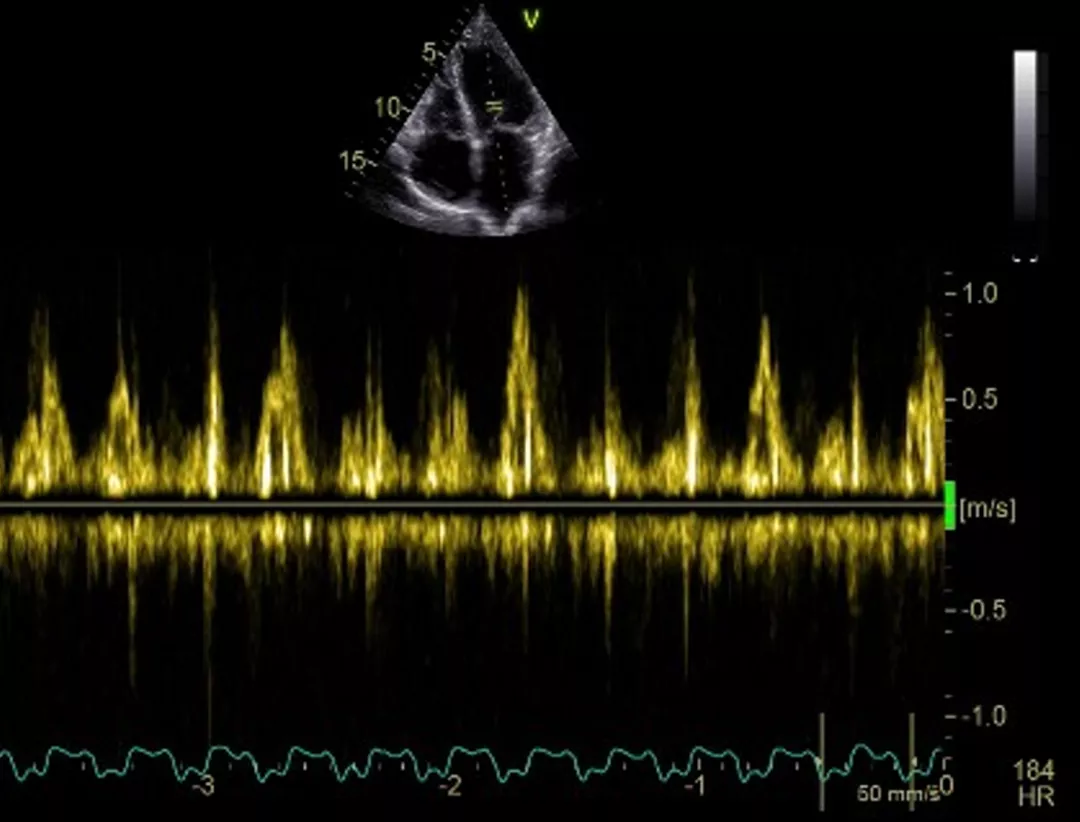

Obr. 3. Zatím definitivní stav: původní stimulační systém DDD zprava, z levé strany CRT-D.